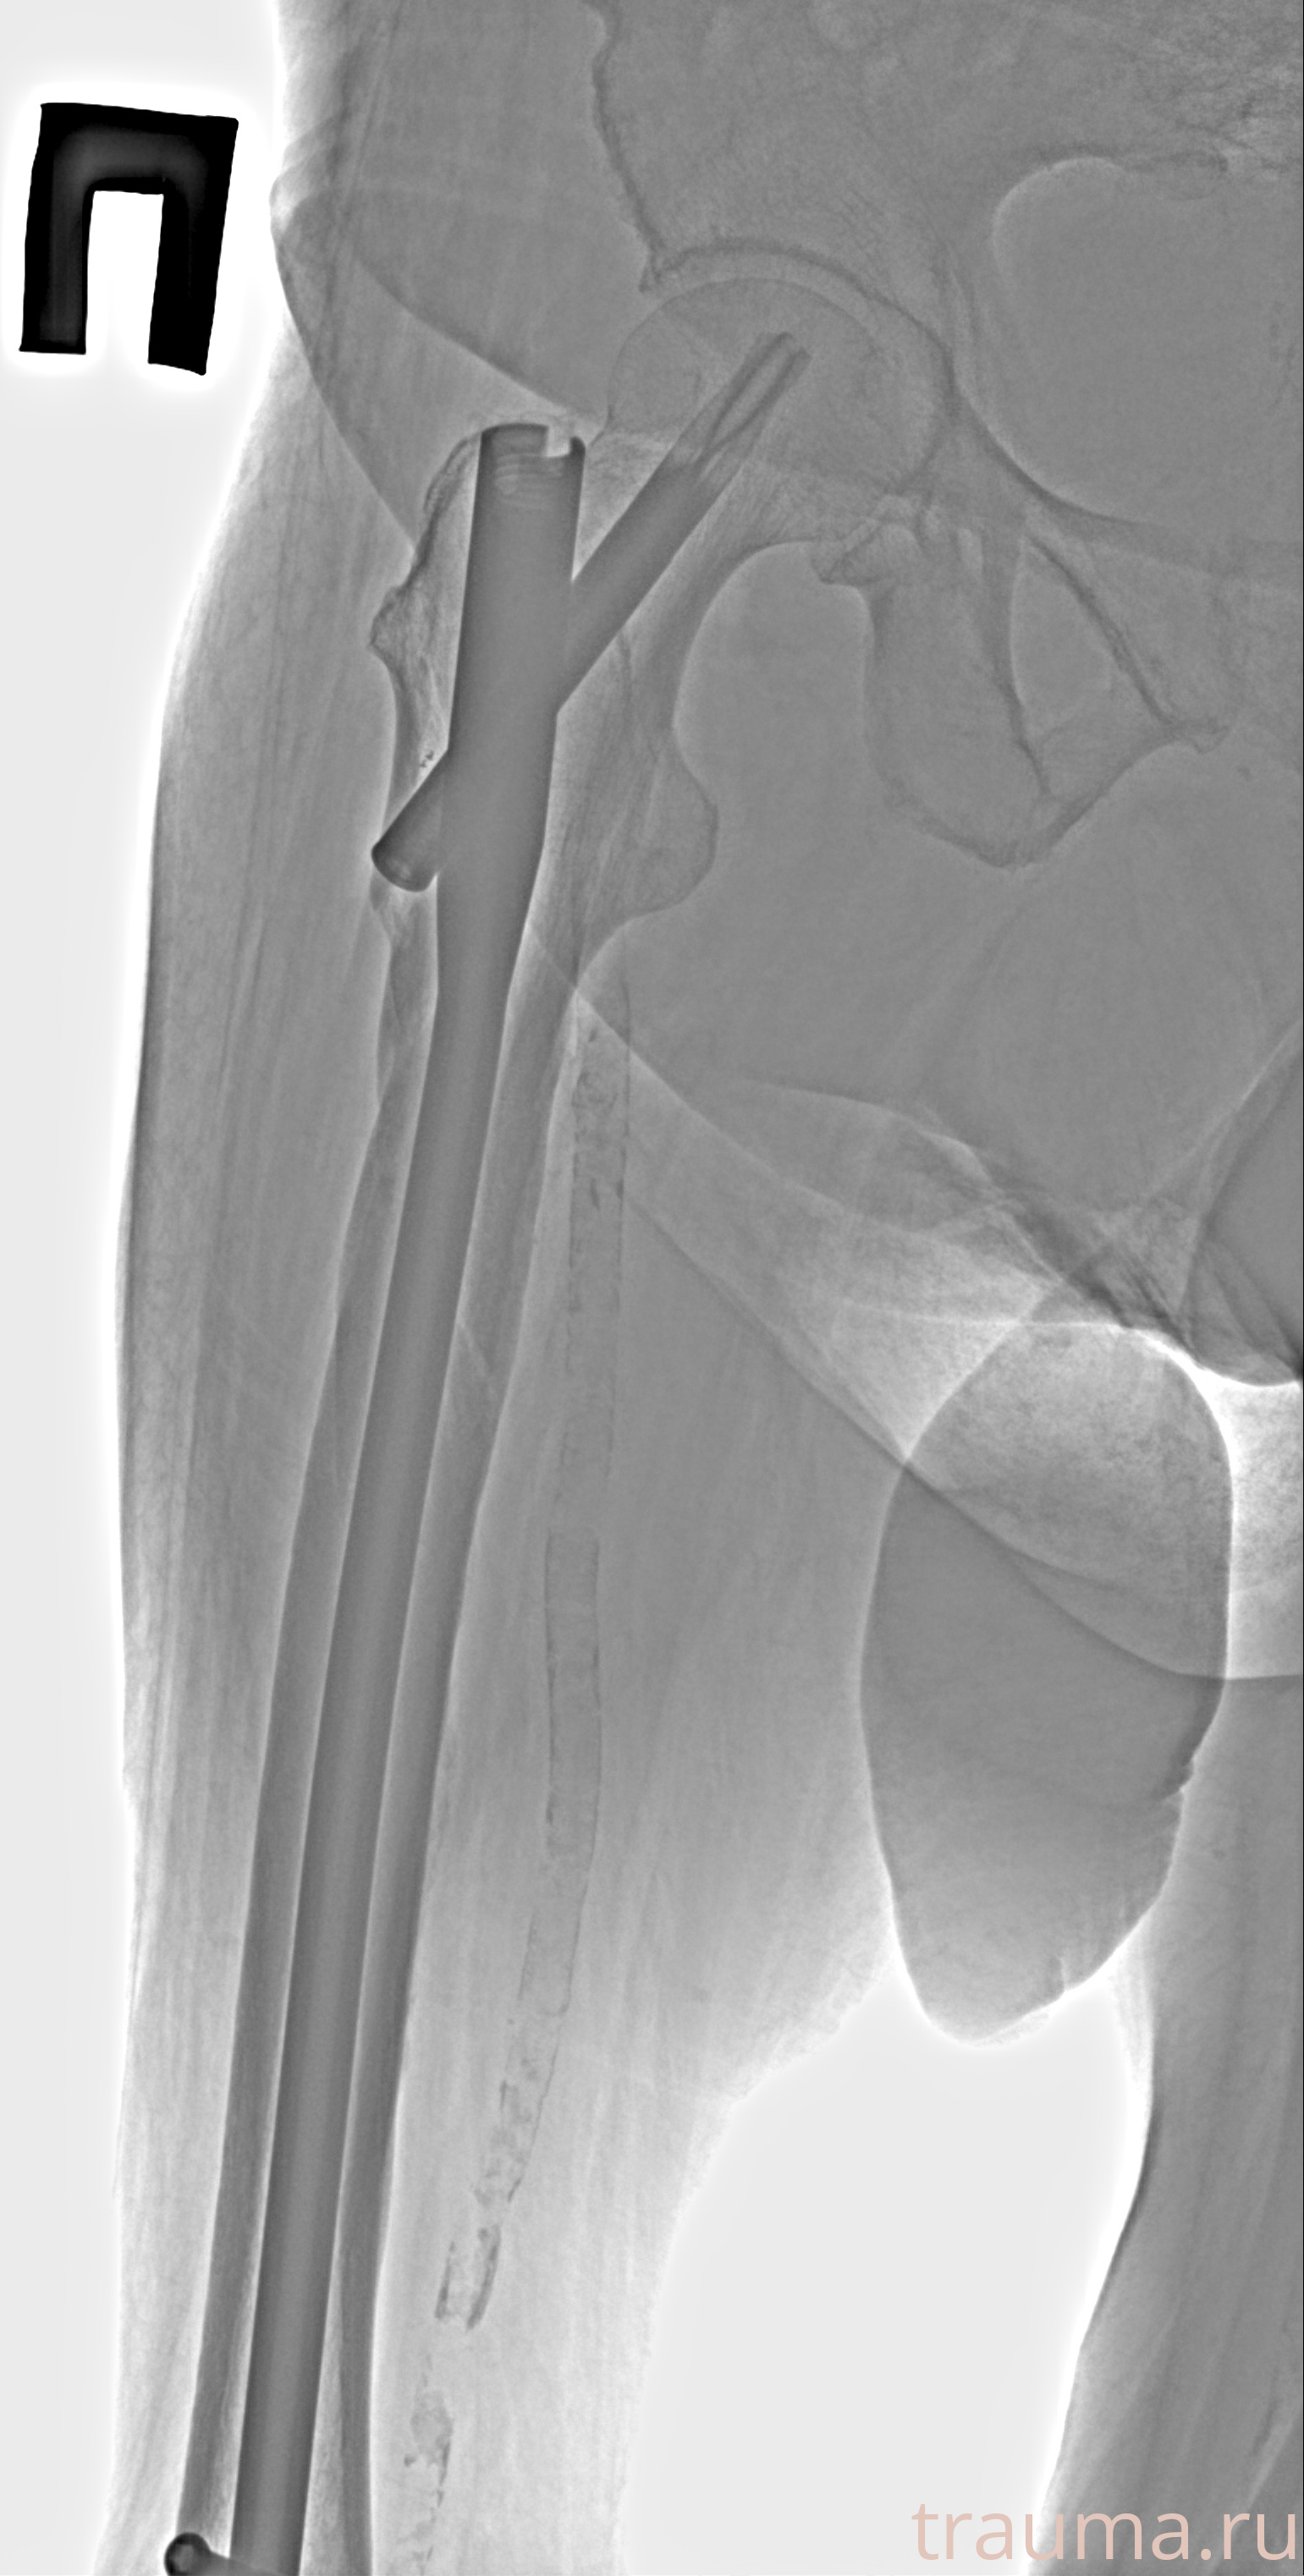

Рентгенограммы

Рентген на дому: по вашему адресу приезжает врач-рентгенолог, травматолог-ортопед с мобильным рентгеновским аппаратом, проводит диагностику травмы или заболевания, делает необходимые рентгенограммы, дает рекомендации по дальнейшему лечению. Получить качественные снимки в домашних условиях возможно благодаря уникальной методике, разработанной МосРентген Центром для института  Склифосовского